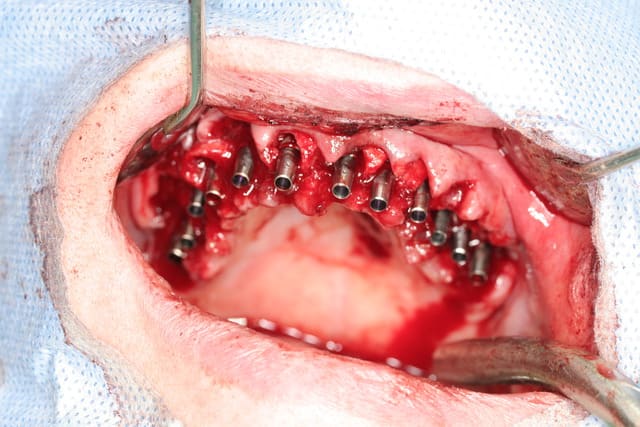

pour combler le gap en vestibulaire prémo canines incisives kasios TCP hp

dans les alvéoles laissées vacantes des molaires, de simples éponges hélostatiques gelatemp Roeko...comme pour une extraction...

pas de greffe de conjonctif, le biotype gingival d'origine étant déjà très sympa

tous les implants sont en diamètre 3.7

certains (j'en fais partie) aiment bien plus large au niveau des secteurs molaire....mais vu que l'on a posé dans les septums, une augmentation de diamètre conduisait obligatoirement à une diminution de la surface de contact os/implant...d'où ce choix...